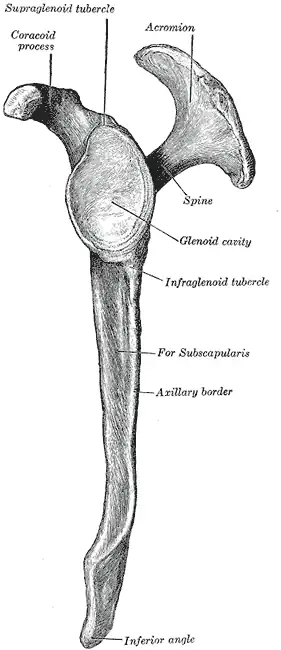

Left scapula. Posterior view. Acromion labeled at top left.

Left scapula. Posterior view. Acromion labeled at top left. -

Left scapula. Lateral view.

Left scapula. Lateral view. -